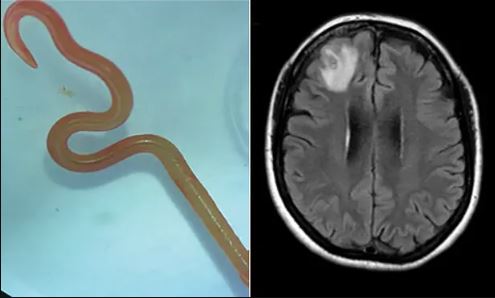

Τα μοντέλα ΑΙ αποτυγχάνουν στις διαφορικές διαγνώσεις στο 80% των περιπτώσεων, κάτι που σημαίνει ότι δεν είναι έτοιμα για κλινική χρήση.